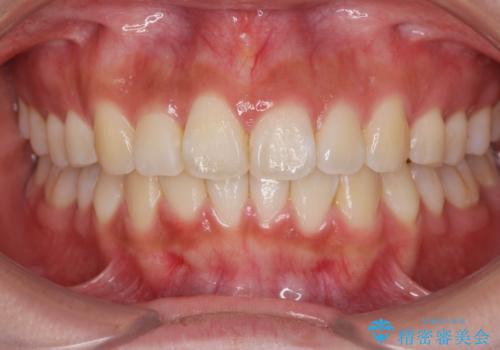

- 前歯の目立つねじれを矯正治療で治したい、と来院されました。

マウスピース矯正を始める前に、ねじれを取るのが短期間で済む部分ワイヤー小矯正を行うことで、全体的な治療期間を短くする治療計画を実行していきます。

前歯のねじれはマウスピース矯正の苦手な動きになり、治療期間が長くなる原因になりやすいです。